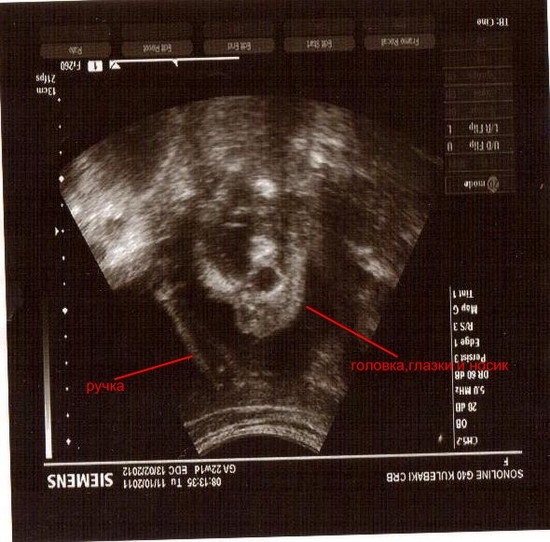

Узи 22 день цикла

Узи 22 день цикла 119 фотографий